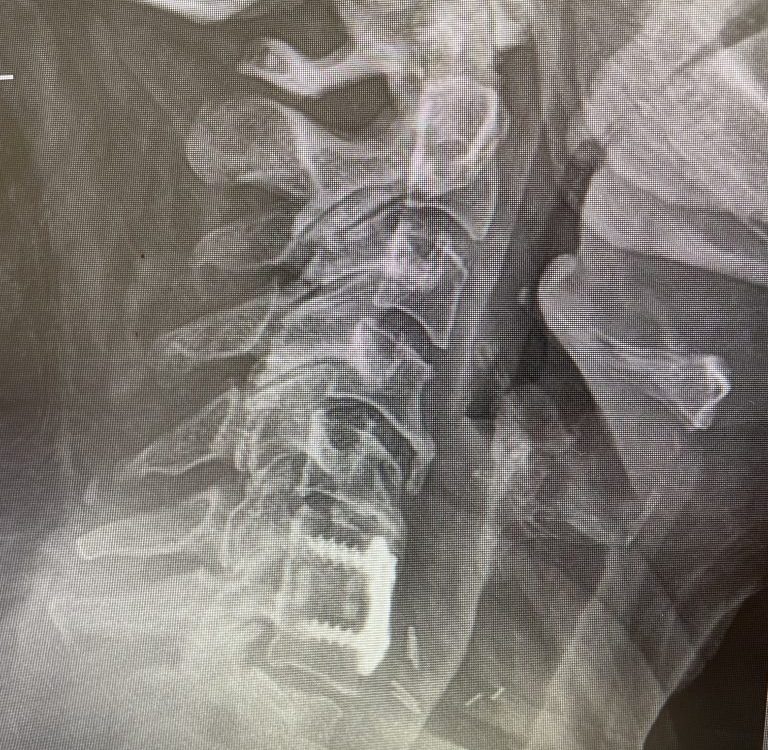

Here is a tough case: This is a 72 year-old male who presented with several months of progressive neck pain without symptoms of the arms or legs. […]